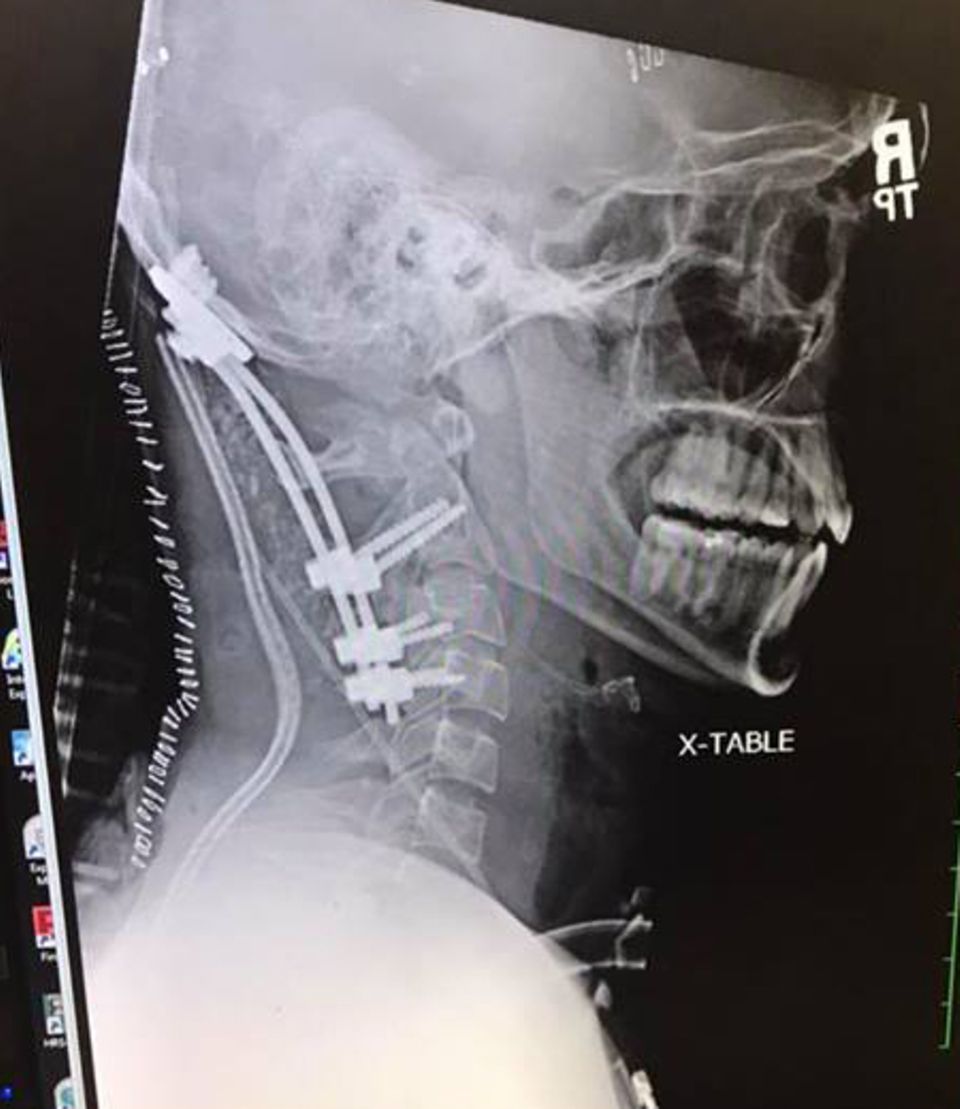

Was er zu diesem Zeitpunkt noch nicht wusste: Seine inneren Verletzungen waren schwerer als gedacht. Die Wucht des Aufpralls hatte seinen Schädel buchstäblich von der Wirbelsäule gerissen. In Fachkreisen wird diese Verletzung atlantookzipitale Dislokation genannt. Mit anderen Worten: eine innere Enthauptung.

Anders bei Brock: Die Rettungskräfte erkannten den Ernst der Lage, sicherten Kopf und Nacken mit einer Halskrause und brachten ihn in das "Memorial Hospital". Dort war Brock nur sechs Jahre zuvor wegen seiner Krebserkrankung behandelt worden. In einer Operation fixierte ein Ärzteteam den Kopf des jungen Mannes mit Schrauben - und der Eingriff glückte. Im Februar konnte Brock das Krankenhaus verlassen. Mittlerweile konnte er auch seine Halskrause ablegen.